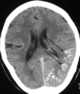

Dural calcification